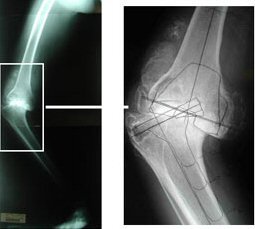

The lives of some elderly people are rendered miserable by progressive bow-leg deformity brought on by arthritic destruction of both knee joints.

Total knee replacement offers a chance for a return to a near normal life, but can be demanding on the surgeon when the condition has been allowed to progress to extremes.